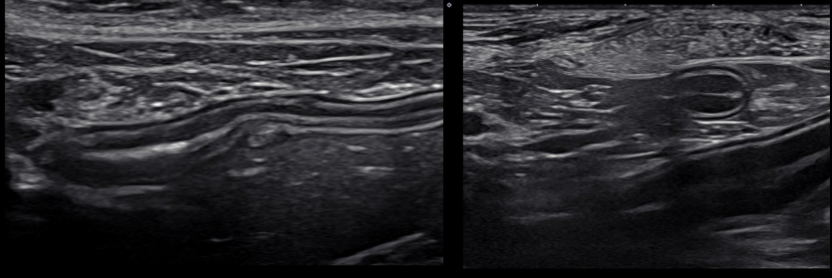

Linear

Rectangle shaped image

Used in small animals where we want to zoom in on small structures

More detail

Tend to be higher frequency

e.g cats